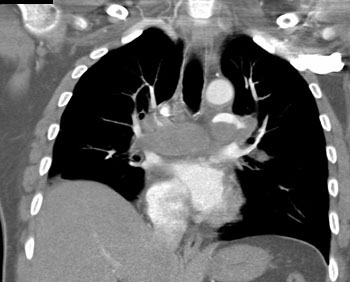

|  | Question 13: A 55 year old man with past medical history of pulmonary hypertension, systemic hypertension, and hyperlipidemia presented with dyspnea. A contrast enhanced computed tomography (CT) scan revealed bilateral pulmonary emboli. Patient was started on anticoagulation and discharged home uneventfully. A repeat CT weeks later suggests? |